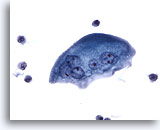

Lavage du bassinet, négatif

Les lavages avec 50 ml de solution saline avant la manipulation de la vessie donnent généralement des échantillons riches en cellules.

20x

Lavage du bassinet, négatif

Les lavages avec 50 ml de solution saline avant la manipulation de la vessie donnent généralement des échantillons riches en cellules.

20x